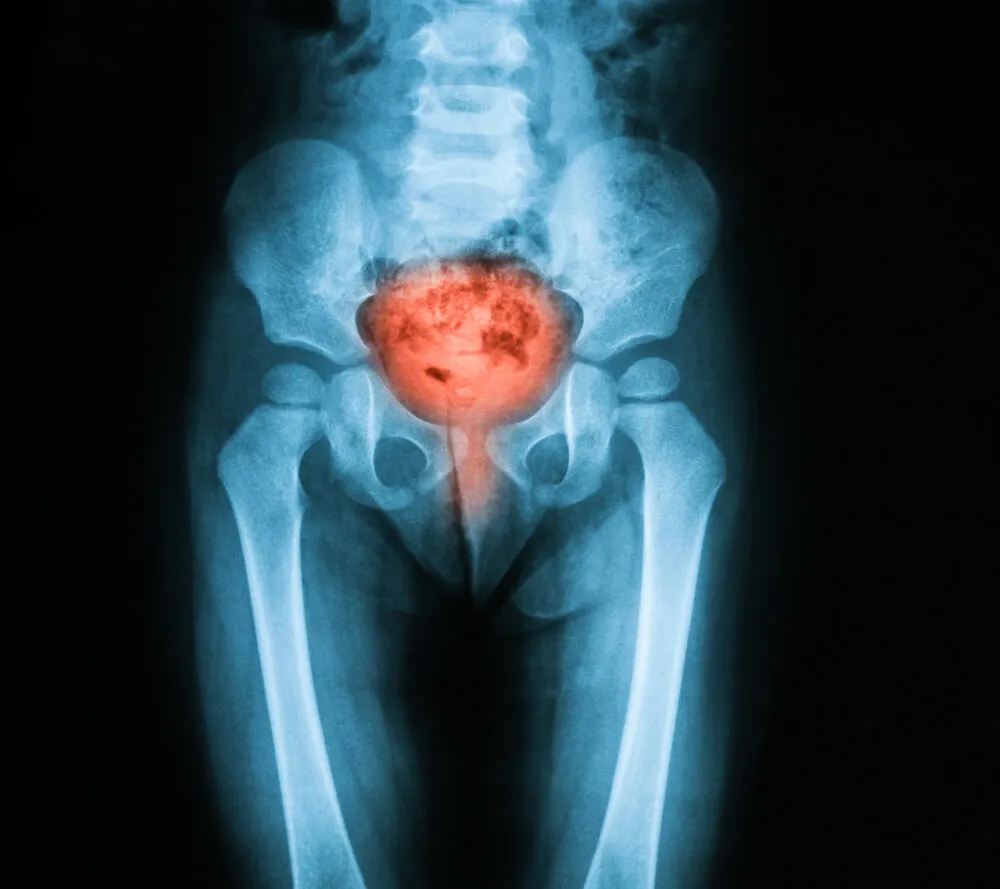

A cistoscopia é um procedimento cirúrgico que permite visualizar o interior da bexiga e a uretra, ou seja, o tubo que transporta a urina para o exterior do corpo. Isso é feito inserindo um tubo fino que possui uma lente e luz.

A cistoscopia é um procedimento cirúrgico que permite explorar a bexiga, a uretra e as aberturas dos ureteres. Estes últimos são os tubos através dos quais a urina passa dos rins para a bexiga. A manobra é realizada com um instrumento chamado cistoscópio.

- Diagnosticar doenças na bexiga ou uretra. Condições como cistite, pedras, câncer, etc. estão incluídas.

- Investigar as causas de certos sinais ou sintomas. A cistoscopia pode ajudar a estabelecer a causa de problemas como incontinência, dor ao urinar, bexiga hiperativa e hematúria ou sangue na urina.